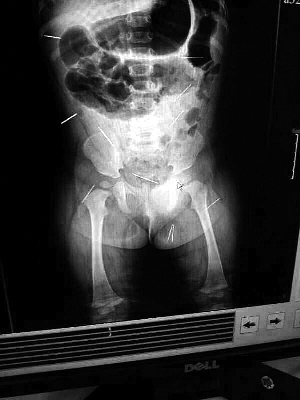

山东聊城11个月女婴萱萱(化名)疑似被人以12根钢针插满臀部、腹腔等部位,昨天在儿童医院会诊后,医生称3根针靠近胸腔最危险,首批先行取出,预计将在下周二手术。孩子父母称孩子一直由家人照顾,自家与他人并无冤怨。山东警方表示正在侦破中,不便透露案情。

北京晨报记者了解到,目前体内的12根钢针多分布在孩子的臀部,一根在腹部,其余3根在胸腔附近,其中一根很接近心脏(如图)。“因为孩子太小,医生们害怕取针的时候对她造成伤害,在胸腔附近的3针可能会威胁她的生命”。